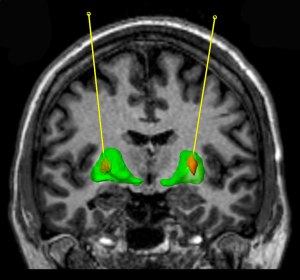

GDNF was pumped into the striatum (green area). Source: Bankiewicz lab

Glial cell-derived neurotrophic factor (or GDNF) is a neurotrophic factor (neurotrophic = Greek: neuron – nerve; trophikós – pertaining to food/to feed). It is a chemical that is produced in the brain. GDNF has previously been found to have miraculous effects on some of the neurons in the brain that are most affected by Parkinson’s disease (particularly the dopamine neurons – Click here to read a SoPD post about this).

The study involved participants having GDNF (or a placebo drug) pumped directly into their brains, into an area called the putamen. The putamen is where the greatest loss of dopamine occurs in people with Parkinson’s disease. All together there were 41 people with Parkinson’s disease enrolled in the clinical trial. The trial was divided into two phases: during the first phase 35 participants received either GDNF or a placebo drug over 9-months in a double blind fashion. In the second phase of the study, everyone received GDNF.